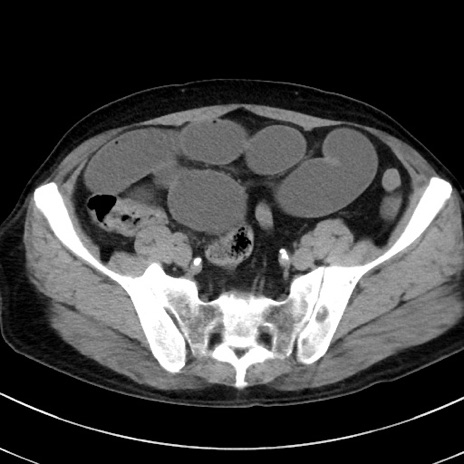

冠状断像

【症例】70歳代 男性

【主訴】腹痛・嘔吐

【現病歴】昨晩より、嘔吐・腹痛あり。今朝になっても嘔吐あり。来院。

【既往歴】心臓バイパス手術、開腹胆摘、腸閉塞

【身体所見】BP 107/71mmHg、HR 116/min、腹部:平坦、軟、下腹部に軽度圧痛あり。反跳痛なし。

【データ】WBC 15100、CRP 0.32